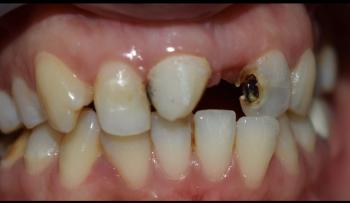

Bite/Alignment Insight

Lower teeth appear crowded.

Potential occlusal interference (teeth hitting with excessive force).

This can worsen mobility over time.